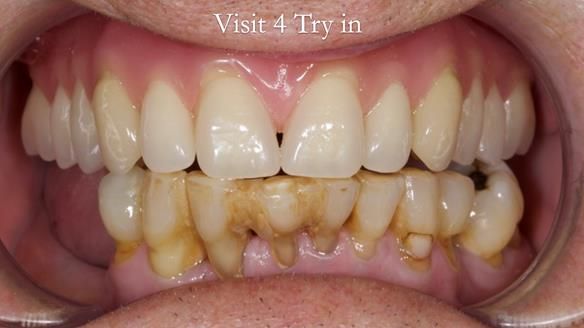

Welcome to my Newsletter 54 showing the making and fitting of dentures (a complete upper metal reinforced denture, a lower immediate partial denture and a definitive Scandinavian designed, metal based lower partial denture) for David, a 75 -year-old man. The full protocol workflow is presented including the use of dentate photographs to mimic his natural teeth.

The clinical situation and treatment process is shown in detail below. I provided the clinical work. Rowan Garstang, my dental technician, provided the technical work.

Interestingly we found that the upper complete denture when finished and fitted didn’t have good enough retention for David’s satisfaction. It was relined by adding compound to the buccal flanges – to almost overextend into the sulcus to ‘create’ a sulcus, followed by using a light bodied silicone impression material. This improved the function of the C/-considerably. A lower Scandinavian hygienically designed lower RPD was also provided which helped with occlusal stability and reseating the upper denture – further improving the fit.